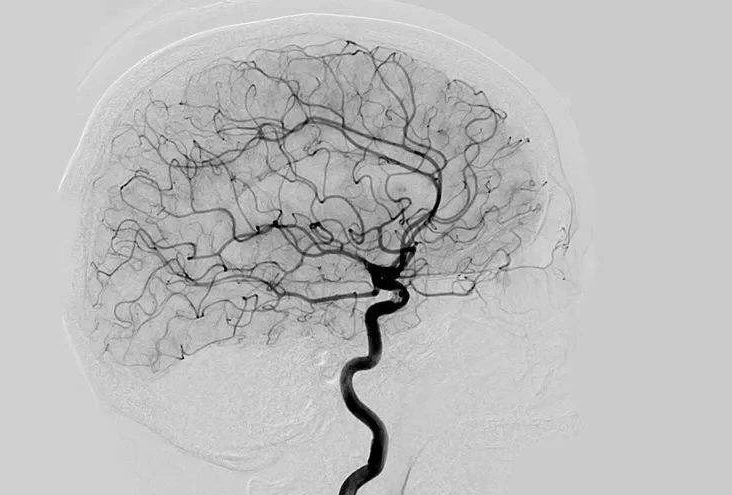

Digital Subtraction Angiography 血管造影機應注意什么?

Digital Subtraction Angiography 血管造影機又稱數(shù)字減影血管造影機,是通過電子計算機進行輔助成像的血管造影方法,應用計算機程序進行兩次成像完成的。在注人造影劑之前,第一次成像工作,圖像轉(zhuǎn)成數(shù)字信號儲存,注人造影劑后,再次成像并轉(zhuǎn)換成數(shù)字信號,兩次數(shù)字相減,消除相同的信號,得到只有造影劑的血管圖像。臨床主要應用于冠心病、心律失常、瓣膜病和先天性心臟病的診斷和治療。